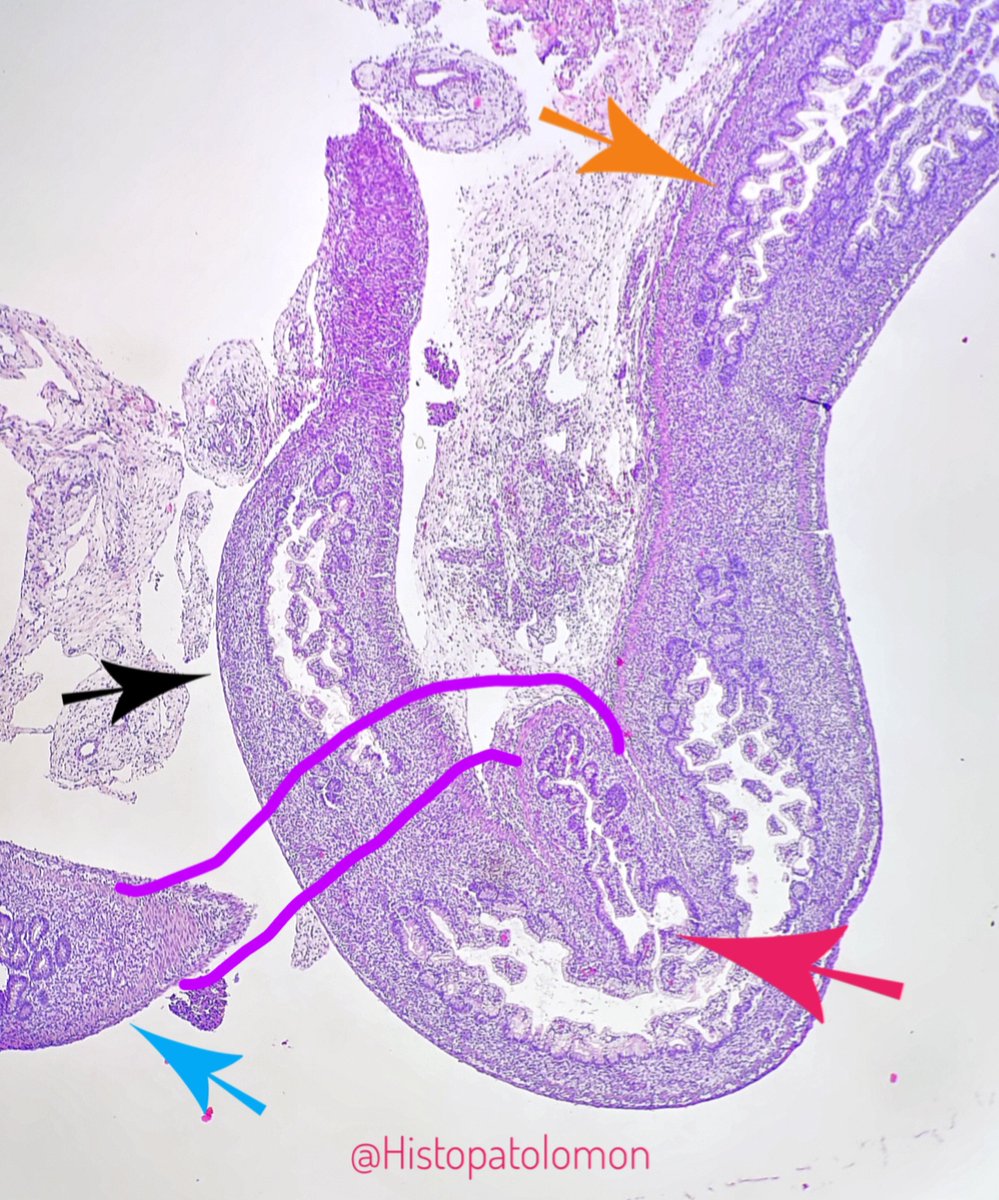

Peyer's patches are clusters of these follicles. This is a Peyer's patch. Also seen an isolated follicle (red arrow). #GIpath #PatchofPeyer

Here we can see a Peyer's patch next to solitary follicles.

This is the section of Peyer's patch shown earlier. Normally they are 2-3 cm, but they can reach 10 cm

colon (orange), ileum (blue), appendix (black), valve (red)